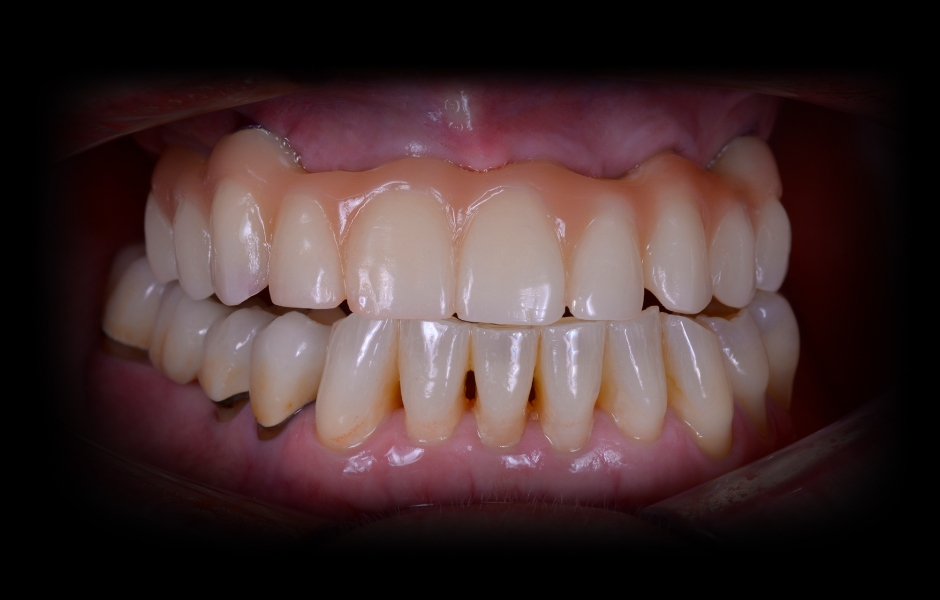

Obr. 1: Klinická a radiologická výchozí situace v horní čelisti se selhávajícími předchozími rekonstrukcemi.

Obr. 2: Klinická a radiologická výchozí situace v horní čelisti se selhávajícími předchozími rekonstrukcemi.

Obr. 3: Klinická a radiologická výchozí situace v horní čelisti se selhávajícími předchozími rekonstrukcemi.

Obr. 4: Klinická a radiologická výchozí situace v horní čelisti se selhávajícími předchozími rekonstrukcemi.